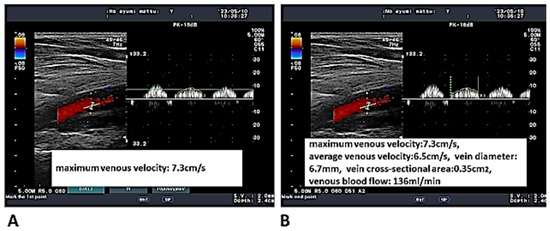

2.3. Measurements of the Deep Venous Velocity and Flow